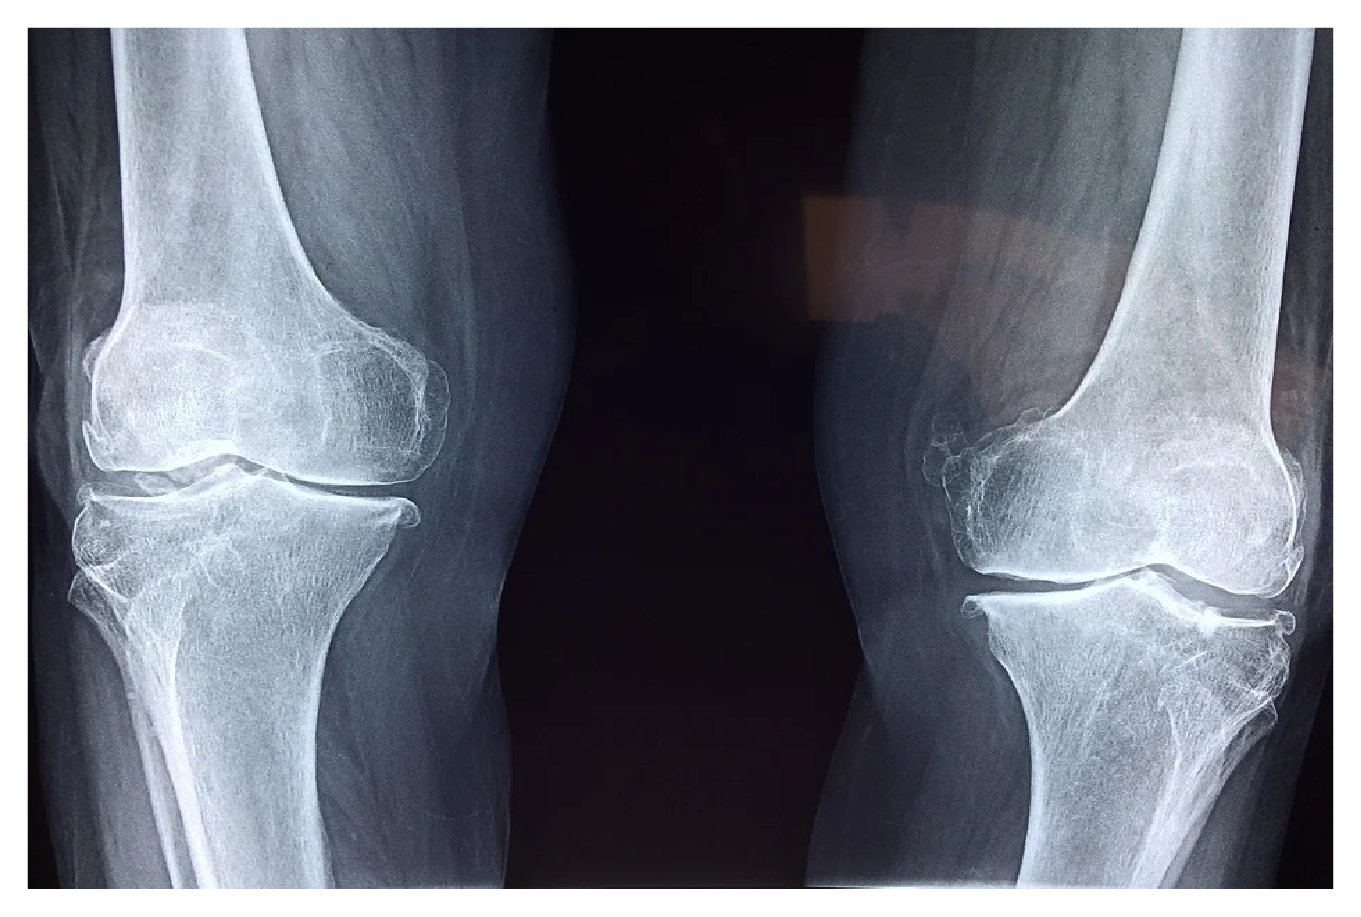

비슷한 이유로 뼈에 금이가거나 골절이 되는 등 뼈에 대한 여러 가지 문제가 발생할 수 있습니다. 따라서 뼈 건강이 약해졌을 때에는 너무 활동적인 신체 활동은 하지 않은 것이 좋습니다.